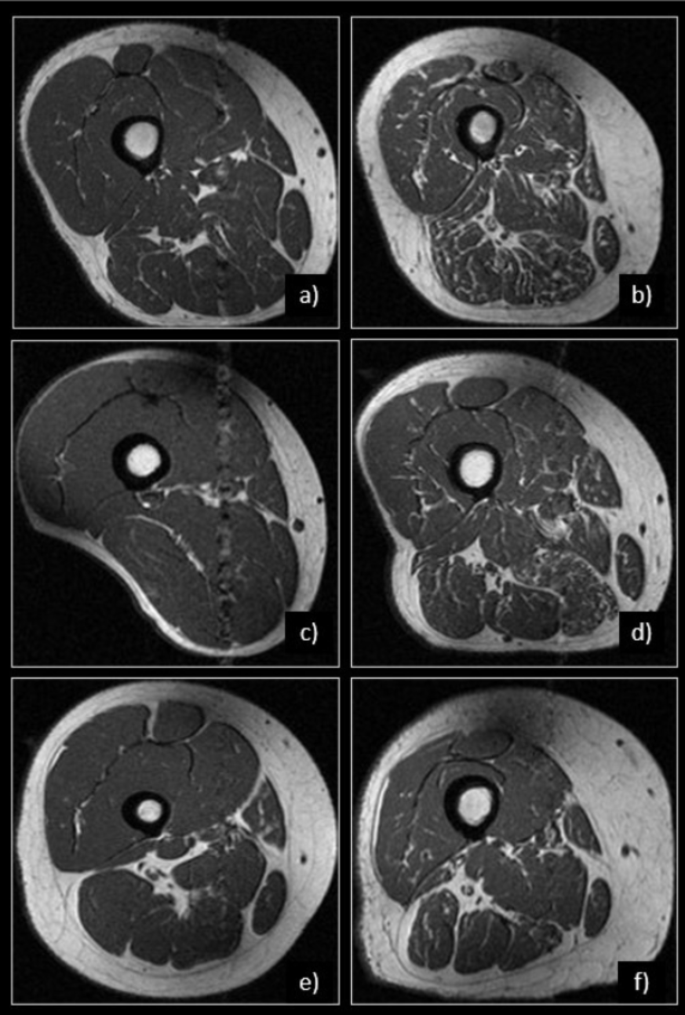

Row 1: men vs. women. Representative MR images of right thighs from 65-year-old man (a) and a 61-year-old woman (b), both with a of BMI = 34 kg/m2 are shown. Note the abundance of fatty streaks in all muscle groups, particularly in the hamstrings in (b) compared to (a). GGs in (b) ranged from 2–3 for all muscles, while GGs in (a) ranged from 0–1 for all muscles. Row 2: normal weight vs. obese. Representative MR images of right thighs from a 58-year-old man with BMI = 19 kg/m2 (c) and 60-year-old man with BMI = 36 kg/m2 (d) are shown. Despite similar ages in both men, higher GGs, ranging between 1 and 3, were recorded in the participant with higher BMI (d) compared to the lean participant (c) with GGs ranging between 0 and 1. Row 3: younger vs. older. Representative MR Images of right thighs from a 48-year-old woman with BMI = 32 kg/m2 (e) and a 71-year-old woman with BMI = 31 kg/m2 (f) are shown. Note the higher abundance of fatty streaks within all muscle compartments in (f), representing increased intramuscular fat with older age. GGs ranged between 0–1 in (e) and 0–3 in (f).